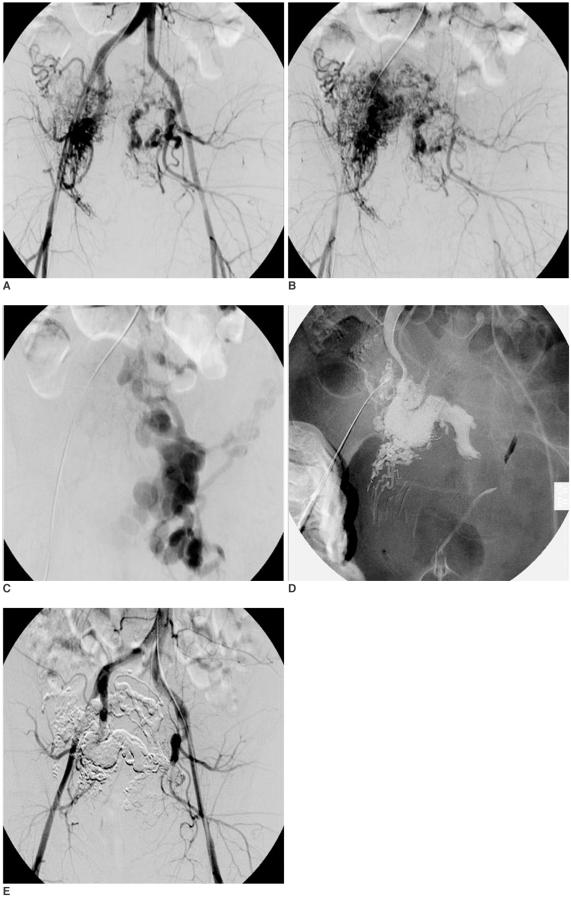

During the past 10 years, eight patients (8 females, age range: 27-52 years) with AVMs in the pelvic wall (n = 3) and uterus (n = 5) underwent staged ethanol embolizations (range: 1-5, mean: 2.5) under general anesthesia. Ethanol embolization was performed by the use of the transcatheter and/or direct puncture techniques. Clinical follow-up was performed for all of the patients, and imaging follow-up was available for seven patients. The therapeutic outcomes were established by evaluating the clinical outcome of the signs and symptoms, as well as the degree of devascularization observed on post-procedural angiography.

During the 20 sessions of ethanol embolization, the solitary transarterial approach was used 14 times, the transvenous approach was used three times and direct puncture was used once. For two patients, the transarterial and transvenous or direct puncture approaches were used together in one session. For four patients, ethanol and coils were used as embolic agents, and n-butyl cyanoacrylate (NBCA) and ethanol were used in one patient. Seven (88%) of eight patients were cured of their AVMs and one patient (12%) displayed improvement. Major complications were seen in two patients (25%).